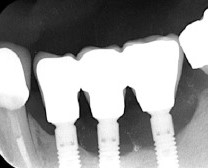

Контрольный снимок — ортопантомограмма:

Рекомендации после операции можно посмотреть здесь>>

Первый этап имплантологического лечения завершён.

К следующему этапу мы подойдём через 3-4 месяца. Этого времени достаточно для интеграции имплантата и регенерации субантрального пространства после синуслифтинга.